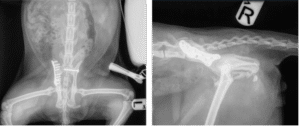

Once Remy was well enough for anaesthesia, surgery was performed to stabilise his pelvis. A sacroiliac screw was placed to address the luxation, and a specialised feline pelvic fracture plate (FLIP plate – designed by Fusion) was used to repair the right iliac body fracture, making the repair more straightforward than traditional systems.

Seven weeks post-op, Remy is now walking confidently again. He is comfortable and pain-free, although he has lost some muscle mass in his hindquarters. Follow-up radiographs show good fracture healing, and he is now gradually being given more space to move around, helping him rebuild strength before full access to the house is allowed again.

Post-operative radiographs